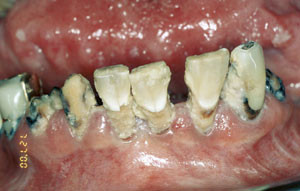

Det er velkjent at bisfosfonater er meget effektive i å redusere symptomer og komplikasjoner ved metastatisk beinsykdom hos pasienter med brystkreft, prostatakreft og multiple myelomer (20). Imidlertid er det i den senere tid rapportert osteonekrose i kjevene (avaskulær beinnekrose) som mulig komplikasjon/bivirkning i forbindelse med slik bisfosfonatterapi (21, 22). De fleste rapporterte tilfeller er assosiert med de høypotente bisfosfonatene pamidronsyre og zoledronsyre og ekstraksjon av tenner under slik behandling (fig 2). Av 36 tilfeller av osteonekrose var 28 (78 %) initiert av tannekstraksjoner (21). Av de resterende «spontane» beineksponeringene synes tynn munnslimhinne å ha betydning, da de fleste tilfellene oppstod på lingualsiden posteriort i mandibelen, et sted med tynn mucosa. Vi har hittil registrert fem tilfeller av bisfosfonatassosiert ostenekrose, alle i underkjeven, fire etter tannekstraksjoner og ett etter oralkirurgisk inngrep.

Kjevene er den eneste del av skjelettet som er eksponert for det eksterne miljø via tannkjøttlommer rundt tennene. Dette er foreslått som årsak til at kjevene synes å være mest utsatt for bisfosfonatrelatert osteonekrose (21). Patologiske tilstander i tenner, tannkjøtt og kjever øker kravet til hastighet på beinvevsomsetningen, som ved bisfosfonatterapi er kompromittert. Det synes som om osteonekrose utvikles ved at kjevebeinet eksponeres for munnhulens mikroflora uten å kunne tilheles – beinet blir infisert, pasienten får smerter og større eller mindre beinområder blottlegges. Da det så langt ikke finnes noen effektiv behandling, er pasientene avhengig av periodevis regional debridering og infeksjonskontroll med antibiotika (21).